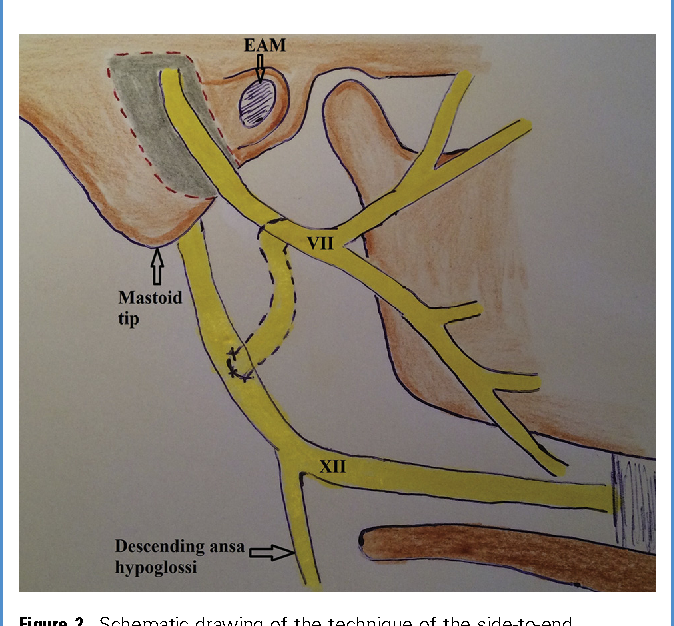

Figure 1 from Comparison of Direct Side-to-End and End-to-End …

Analysis of Preoperative Factors Influencing Hypoglossal-facial ‘Side …

Hypoglossal Facial Anastomosis | Ento Key